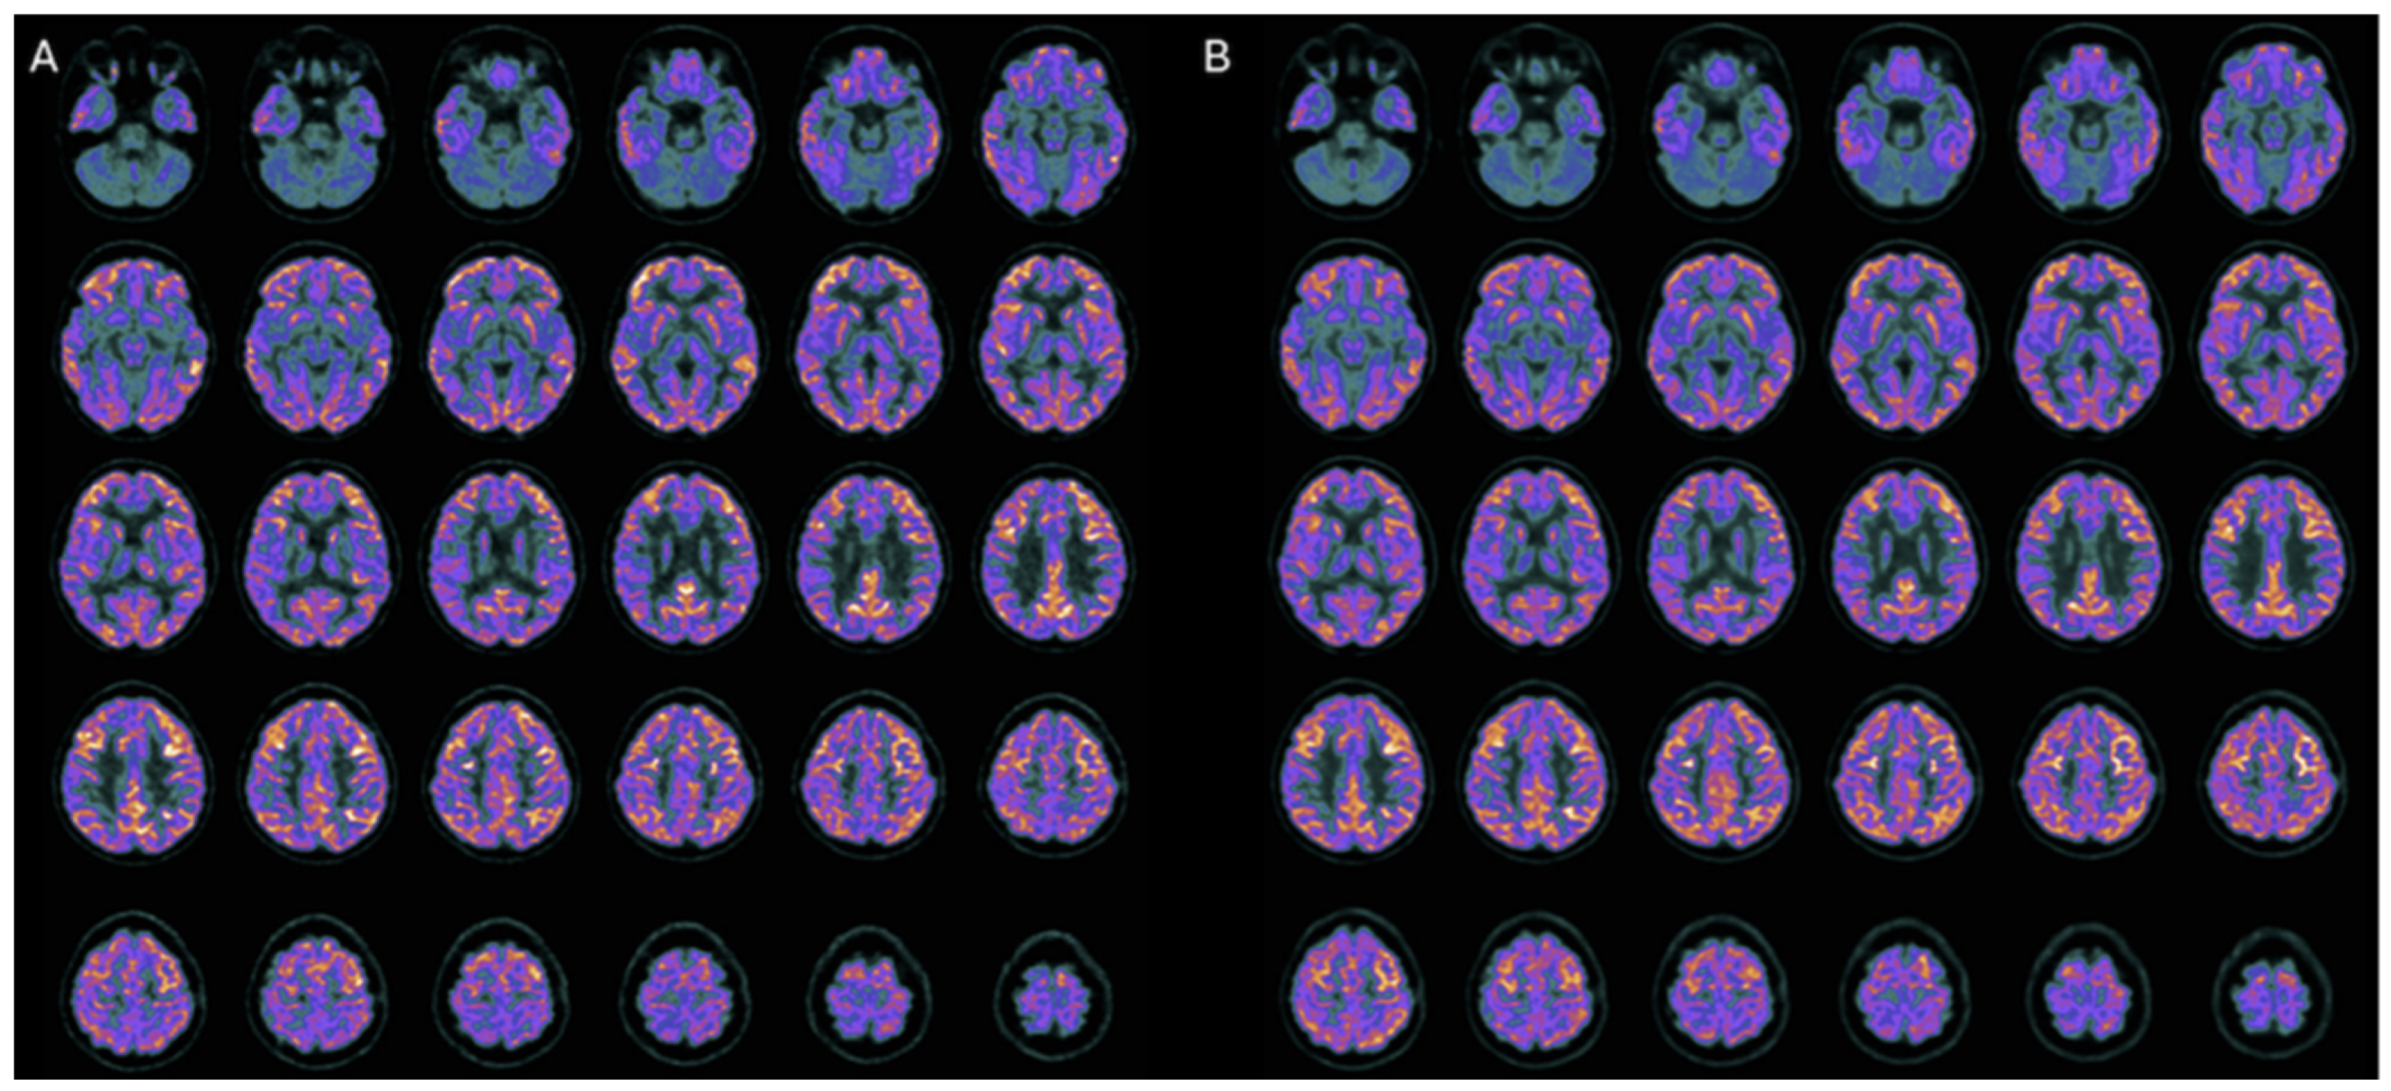

In the fifth case [30], a 14-year-old boy with severe diffuse axonal injury exhibited significant cognitive recovery after intranasal hr-NGF, with improvements in overall intellectual functioning, processing speed, working memory, attention, inhibitory control, visuospatial memory, academic skills, and adaptive behavior [30]. PET showed increased glucose metabolism in the parietal, striatal, and cerebellar regions (Figure 7), while SPECT demonstrated improved perfusion in the caudate nuclei, putamen, and thalami [30]. EEG remained physiologically normal throughout treatment [30].

Figure 7. 18F-FDG PET brain axial slices performed before (A) and after (B) NGF treatment in the fifth TBI patient. Mild reduction in 18F-FDG uptake in the bilateral parietal cortex, subcortical regions, and a slightly more severe reduction in cerebellum (A). After the NGF administration, an increase of the radiotracer uptake in the bilateral parietal cortex (right: +7%; left: +6%), right and left caudate nucleus (right: +3%; left: +5%), and cerebellum (+6%) was observed (B).